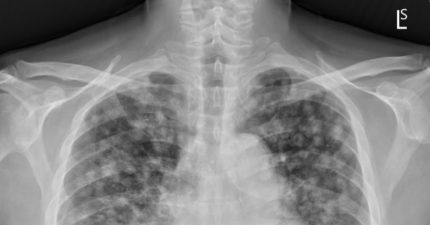

每年都照X光!50歲男「現1症狀」仍確診肺癌末期 醫驚:千百顆滿天星

August 27, 2025

台灣, 知識